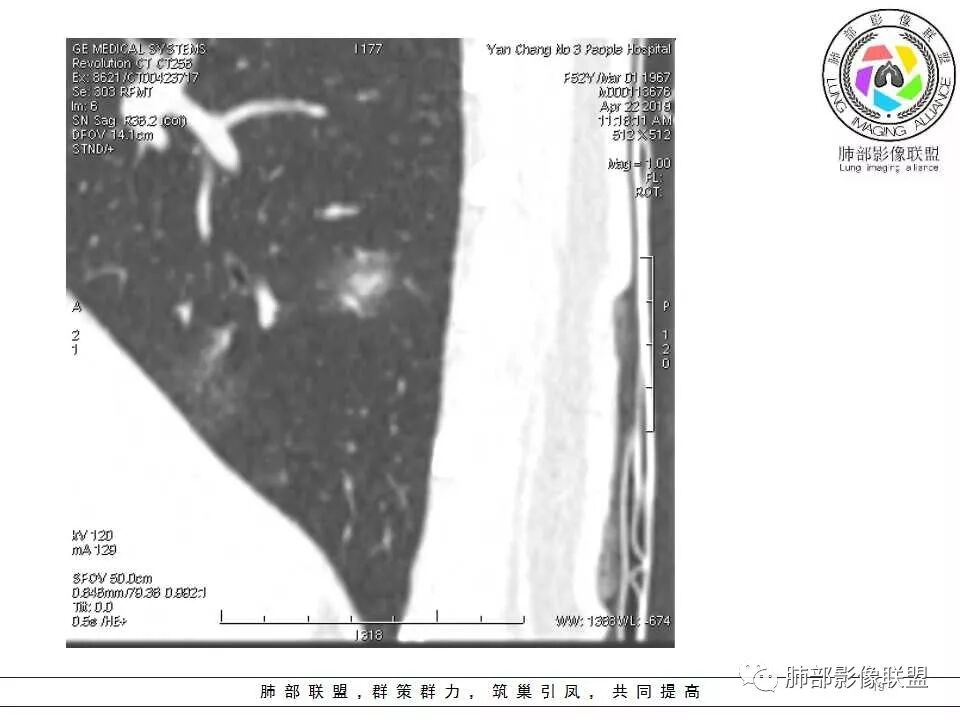

横断位看上去晕很模糊,冠矢状位重建后却比较清晰,所以单次CT检查蛮难定的,中心透亮区一定是空洞吗?我怎么觉得是一支气管壁有增厚,管腔有轻度扩张的支气管,第一感觉还是炎性结节吧,PC可能大,一定要否定腺癌也不敢,一个月左右复查。

体检发现肺部结节,右下肺混合密度结节,结节中心空泡,壁光滑,结节边缘模糊,血管在结节内增粗,矢状位前基底段还有一片磨玻璃影,所以考虑良性结节可能,炎性肉芽肿?抗炎后复查。腺癌合并炎性改变待排。

连续层面显示这个应该是空泡,或者小空洞,远端没有,近端也没有,周围环形软组织增厚。而空泡,影像上只是根据5mm界线,病理上不一定。

假如这是含气支气管,伴随的哪条动脉呢?近端从哪来?为啥环形壁增厚而又不均匀?都不太符合,所以支持空泡或小空洞。

上次刘纯老师提出,空泡征是一个影像征象,不是一个病理征象,我比较支持,他就是一个影像上的小低密度腔,原因很多,但是影像上与小的空洞表现区分不了。其中的原理:有一条是内容物排出后的残腔,其实也是空洞的原理。

大家考虑恶性的依据?炎性的依据?首先这是不是磨玻璃结节?依据是啥?

因为密度比肺组织高,但是又遮盖不了血管,所以GGO明确

是pGGO?mGGO?

实性的部分超过10%——mGGO

GGO边缘清不清?依据?

部分清,部分不清

依据:能不能沿GGO边缘画出一个边界

能否勾勒出边界?是否有血管?

排除血管的边缘,边界清吗?

可惜的是背景也模糊了一些